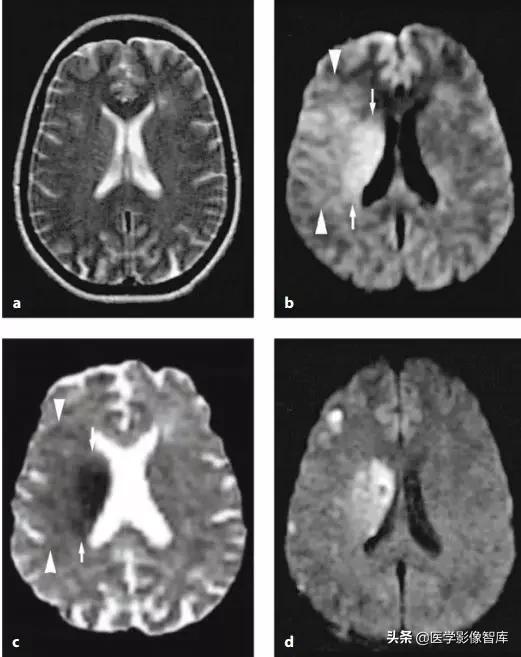

弥漫性脑部缺血 - 缺氧改变

DWI 和 ADC 图是显示早期缺血 - 缺氧脑策划信号改变最好的序列(优于 T2WI 和 FLAIR),早期即有明显的 DWI 高信号及 ADC 低信号改变,最常发生在分水岭区域的皮质 / 皮质下,基底节区也常累及。有明确脑部弥漫性缺血缺氧病史,如心跳骤停,该疾病不难诊断。图 5 为典型影像表现。

图 5 心跳骤停患者,弥漫性脑部缺血 - 缺氧改变,A~D 为 DWI,E~H 为 FLAIR,可见弥漫的双侧皮层高信号。